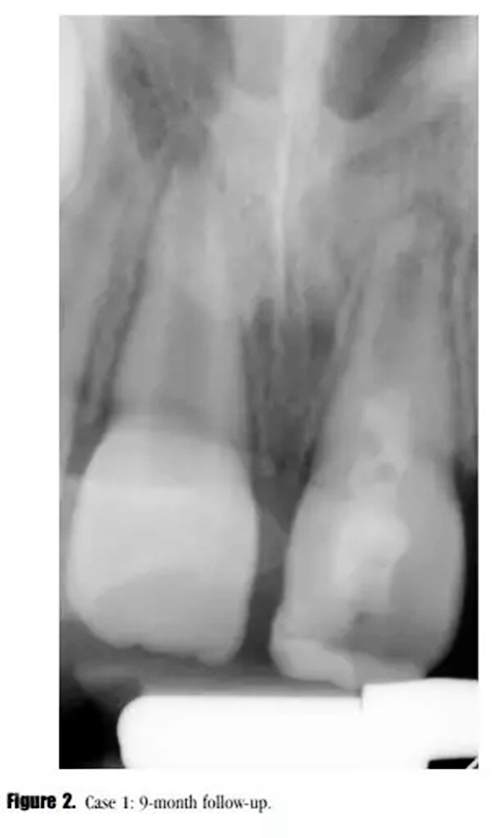

在3,6,9個月的隨后跟蹤隨訪中,患者完全沒有癥狀。與鄰牙和對側(cè)牙對比,21的叩診、捫診以及牙周袋深度都在正常范圍內(nèi)。對于牙髓溫度測試沒有反應(yīng)。影像學評估顯示,根尖區(qū)低密度透射影像范圍減小,牙根發(fā)育為I型(按照Chueh等人的研究)(圖2),